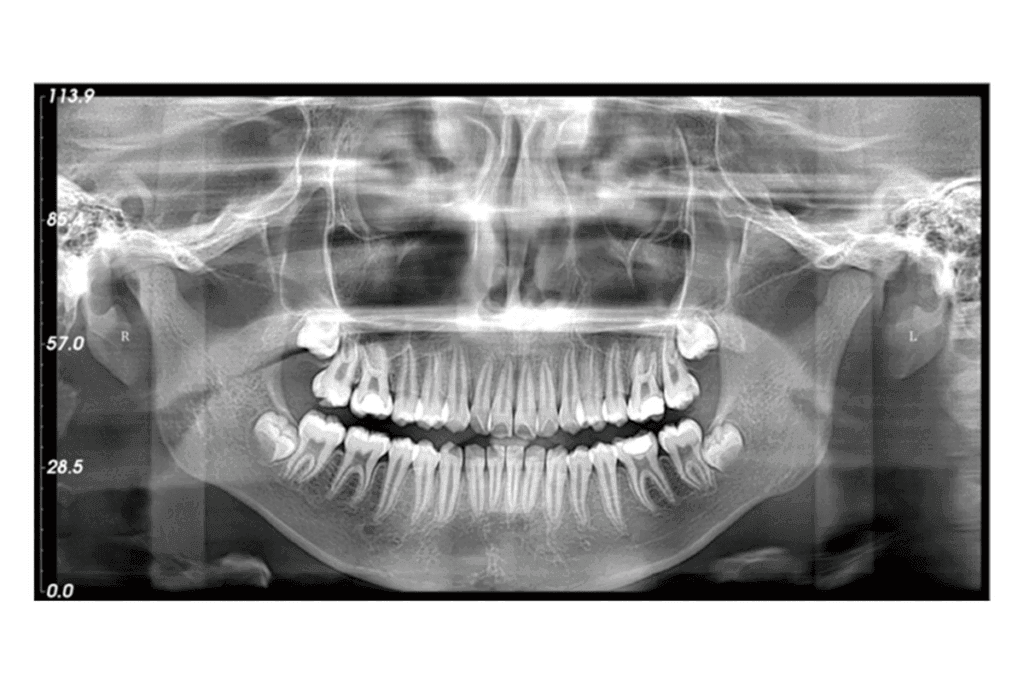

- Panoramic X-rays: Give a wide view of the upper and lower jaw, useful for dental structure and treatment planning.